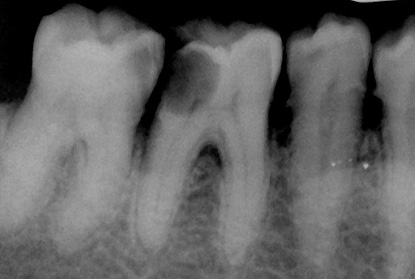

Diagnostica a raggi X: è un metodo abbastanza informativo. Ad esempio, per la natura del cambiamento nella struttura dell'osso attorno alla radice del dente, possiamo capire che abbiamo segni di pulpite e non parodontite, possiamo anche determinare i bordi approssimativi della cavità cariata e suggerire una violazione (apertura) della camera pulpare. Questo è importante per confermare o confutare la diagnosi di carie profonde.

Nelle forme croniche di parodontite, di norma, i cambiamenti nel tessuto osseo intorno alla radice sono significativi e nella pulpite acuta non ci sono tali cambiamenti (con pulpite gangrenosa cronica a volte è possibile una leggera espansione del gap parodontale).